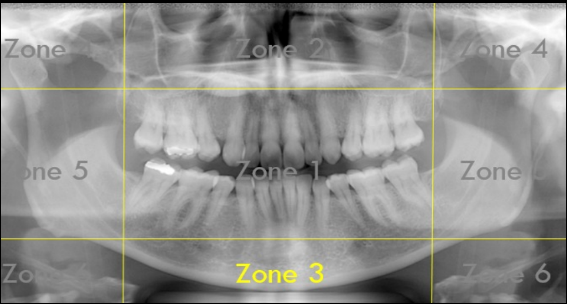

Identify The Zones.

Zone 1: Dentition

Zone 2: Nasal Cavity and Maxillary Sinuses

Zone 3: The Mandible

Zone 4: Temporomandibular Joints (TMJs)

Zone 5: Spine and Ramus

Zone 6: Hyoid Bone

What Zone Is This?

What do we see in Zone 4?